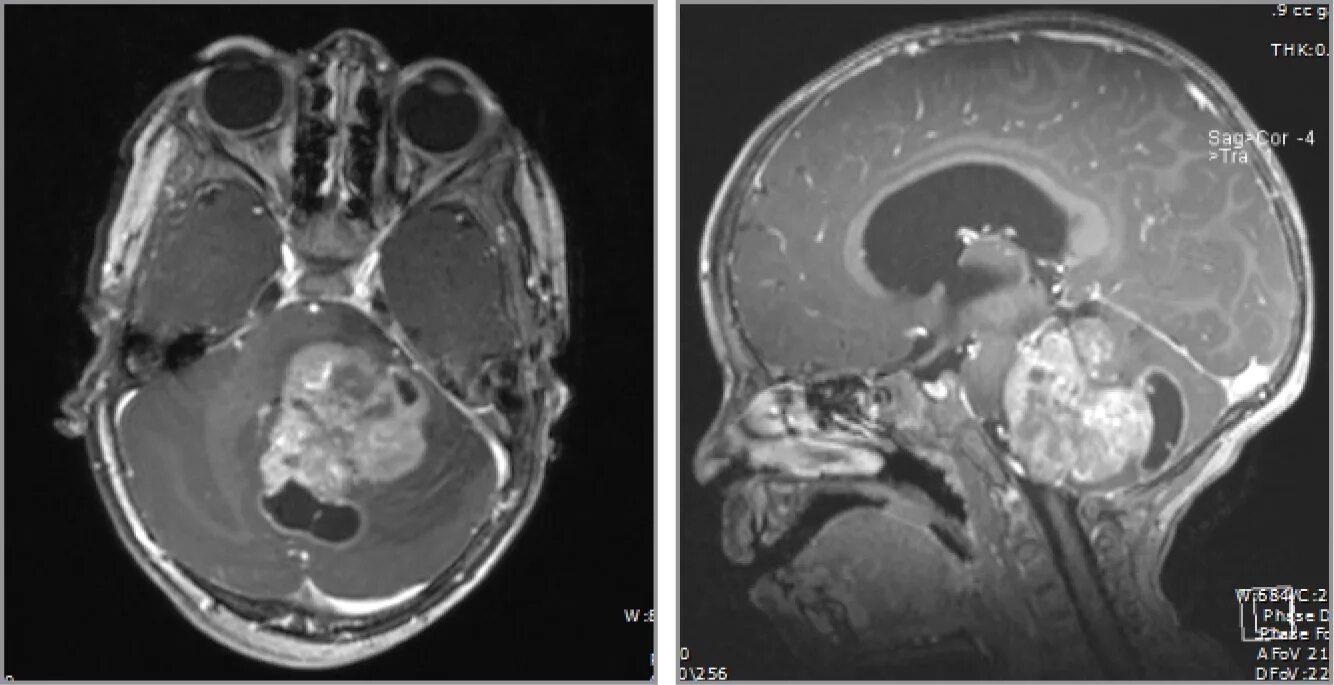

Диффузные кольца